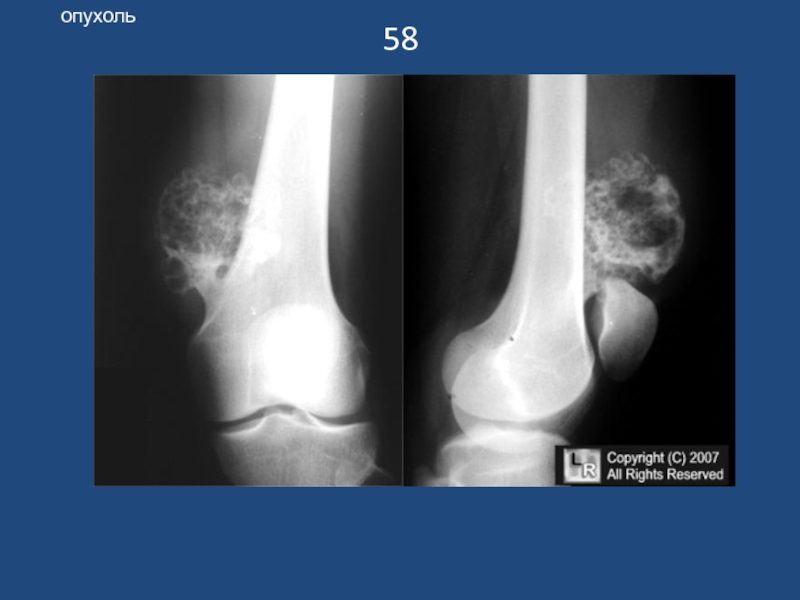

Слайд 5958

опухоль

58опухоль